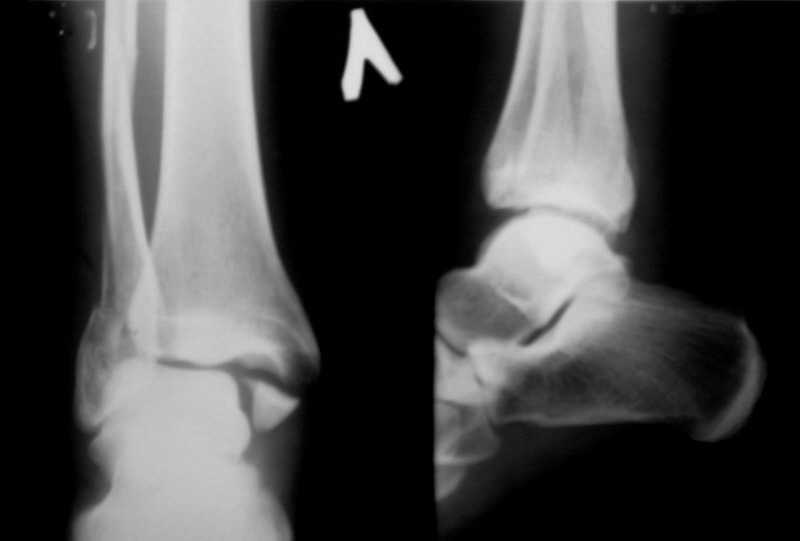

Вот рентгенконтроль на 7-е сутки после репозиции.

Серега, привет! А что наш ув.доцент А.П.М. говорит по этому поводу. И вообще, я не знал, что ты лечишь 3-хлодыжечные задними лонгетами, - нас с тобой учили это делать циркулярными гипсовыми повязками. Все равно, удачи! На контроле, почему-то, все заманчиво хорошо. Не спеши делать выводы

Стандартными снимками считается прямая, боковая и мортиз!!!, а так трудно гадать, насколько потеря длины малоберцовой. На боковом снимке не сопоставленный перелом медиальной лодыжки и перелом заднего края без смещения.

Трехлодыжечные переломы относятся к нестабильным переломам, при вовлечении перелома заднего края больше 15% суставной поверхности и смещения более 2 мм тогда такие переломы необходимо оперировать.

Хорошо сопоставленная закрытая репозиция отломков не гарантирует отличный окончательный результат.

Трудно удержать трехлодыжечные переломы задней лонгетной повязкой (на снимке), а последующие долгие гипсовые повязки могут привести к контрактурам.

Оперативное лечение предупреждает артроз из-за ранних движений, и больные восстанавливается быстрее, чем на консервативном лечении.

Вероятность ошибки при оценке состояние сустава без стандартных снимков возрастает на 30%, поэтому необходимо добиться от рентгенолога всех необходимых снимков.